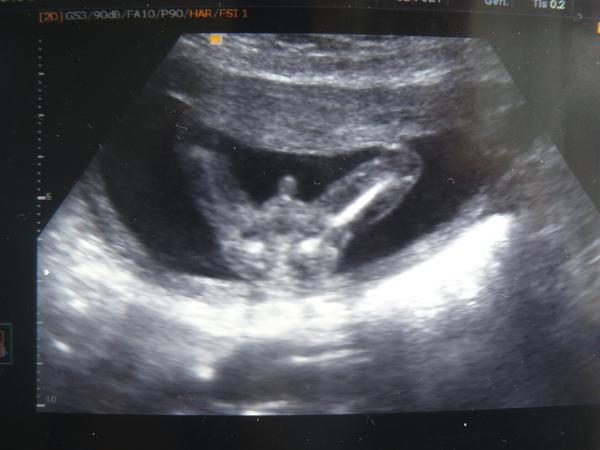

Taky na ultrazvuku vidíte klučinu?

Ahojda,byla jsem na utz a chtěla jsem vědět co druhé mimčo je .... Doktor na mě otočil monitor a říkal že to poznám i já,že je to klučina . Ptám se proto,zda vidíte fakt klučinu nebo to muže byt třeba pupečník ?

Tohle je kluk, podivej na linii zadecku, presne uprostred je pindik. Tohle je chlapak, vidim i pytlik 🙂

Má ho tam! Leda by pupečník měl i kuličky😀.

Buď si s tam s sebou přibalil jojo a to co holky identifikují jako pindíka je provázek a kuličky jsou samotné "jojo", nebo je to kluk. Jsem nadšenec do joja, je to určitě jojo 😀 Ne, dělám si srandu. Tohle je jasnej chlap. Co se v mládí naučíš, ve stáří jako když najdeš a tak si můžeš být jistá, že ho takto bude ukazovat často po celý svůj život! 😉

@radova23 Tak tohle je opravdu chlapecek 🙂 ja to takhle mela dvakrat 🙂